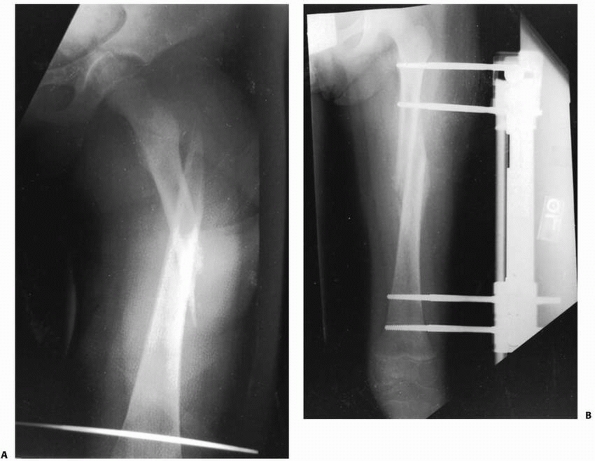

![]() |

FIGURE 22-8 A. A proximal spiral femur fracture, which failed treatment with pins and plaster. B. Salvaged with an external fixator.

FIGURE 22-20 AP (A) and lateral (B)

x-rays a low-energy short oblique fracture through a fibrous cortical defect in the distal femur; this type of fracture is not unusual. The surgeon judged that there was enough distance between the fracture site and the growth plate to allow external fixation. AP (C) and lateral (D) x-rays 3 weeks after external fixation shows early callus and good alignment. The external fixation was removed shortly after this x-ray and the child was placed in a long leg cast, with weight bearing as tolerated. |